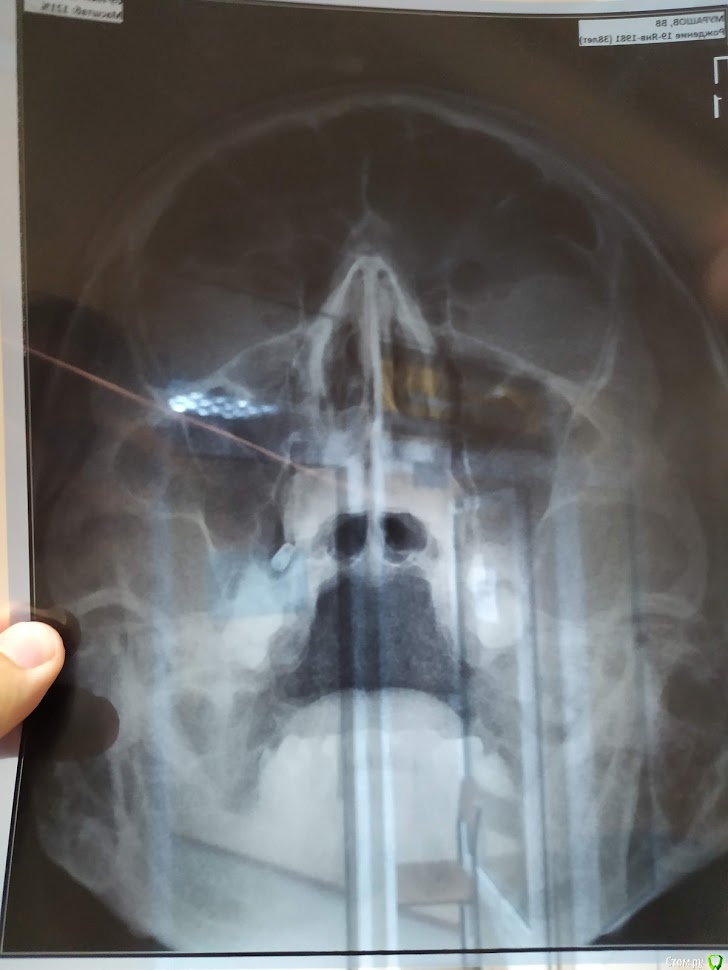

Валдемар Опубликовано 29 августа, 2019 Поделиться Опубликовано 29 августа, 2019 Добрый день,Уже был здесь, но прошлые явки и пароли забыл.12.04 операция 4 импланта20.04 вылез первый15.05 вылез второй26.08 удален 3ий28.08 удален 4ыйПотрачено 100тр, время и нервы. Возвращено 7200 за 2 импланта, за 2 которые удаляли деньги не вернули, так как не было показаний. А то что голова болит, переносица, лоб - ет не от этого. Удалил и всё прошло, кстати.Вопрос:1). Справа десны (кости) реально меньше чет слева. Что с этим делать. Как сделать чтобы кости хоть немного прибавилось? Без имплантации, просто кость с десной нарастить.2) 100% неприживаемости - ето как? Диабет, спид, гепатит по диспансаризации сдавал - отрицательно. Какие мои действия теперь? по новой имплантироваться и если опять не приживется, опять по новой? Ссылка на комментарий

Валдемар Опубликовано 31 августа, 2019 Автор Поделиться Опубликовано 31 августа, 2019 Я снимок после удаления не делал, но у меня реально справа десна тоньще раза в два. Там воспаление месяца два шло. В имплантацию больше не верю, вернее, боюсь. Боюсь нового стресса для организма. Верил в современную медицину, российскую, смотрел на людей с коленками кривыми, тазобедренными суставами проблемными, говорил че вы ждете, щас раз и коленку и тазобед сустав меняют и как новенький, а теперь понимаю, фиг там. Китайское что рибудь поставят, или руки у дохтора не оттудава, и всё, можно на костылях оставшуюся жизнь бегать...Потому люди до последнего и тянут. Ссылка на комментарий